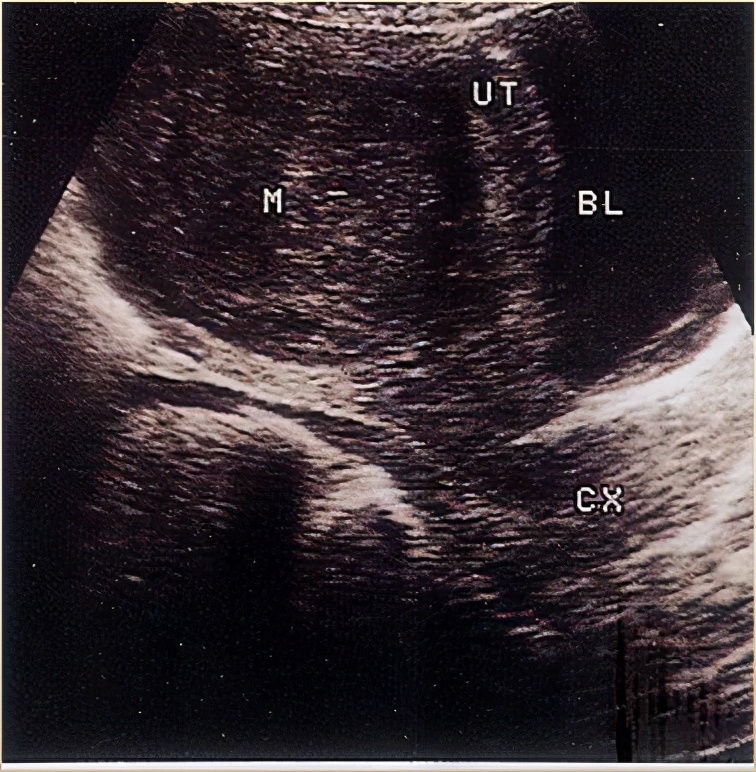

彩超下的子宫肌瘤

子宫后壁较大肌瘤